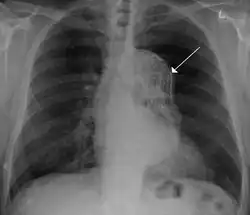

Blunt thoracic aortic injury

Advances in vascular surgery, specifically endovascular technologies, have led to a dramatic change in the operative approach to blunt thoracic aortic injury (BTAI). BTAI results from a high speed insult to the thorax such as a motor vehicle collision or a fall from a height. One widely-used classification scheme is based on the extent of injury to the anatomic layers of the aorta as seen with computed tomography angiography or intravascular ultrasound. Grade 1 BTAI are those which tear the aortic intima; grade 2 injuries refer to intramural hematoma; grade 3 injuries are pseudoaneurysm and are only contained by adventitial tissue; and grade 4 refer to free rupture of blood into the chest and surrounding tissue.[36] When indicated, first line intervention involves TEVAR.